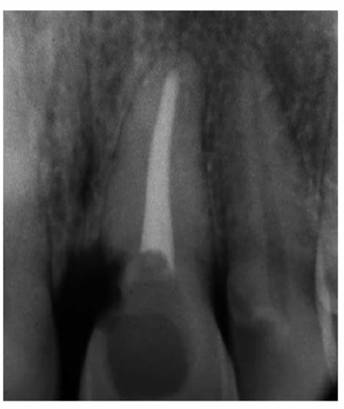

Prior to cementation, Yamada (personal communication, 2001) re-radiographs the

prepared teeth (Figures 19-25A

and B).

These images check the pulpal, periapical, and periodontal status of the teeth.

Also, the radiographs, unencumbered by the presence of the metal castings,

provide a chamber/canal road map record if the tooth requires endodontics in

the future. This may appear pessimistic, but Arens and Chivian reported that

over 40% of teeth requiring root canal therapy are crowned.4 Prior

knowledge of the size, location, and direction of the chamber and the canal will

reduce the possibility of (1) crown damage during access opening, (2) lost time

searching for the canal orifice, (3) perforations of the chamber or the canal

because of disorientation, (4) natural core elimination by gutting, (5) crown

dislodgment, and (6) sufficient destruction to alter the situation and require

corrective surgery. Each of these iatrogenic possibilities reduces the

prognosis and jeopardizes the tooth's reliability as an abutment.

Figure 19-25A and B: Precementation radiographs provide a road map to the canals if endodontic therapy is necessary after cementation of the castings. (Radiographs courtesy of Dr. Henry Yamada.)